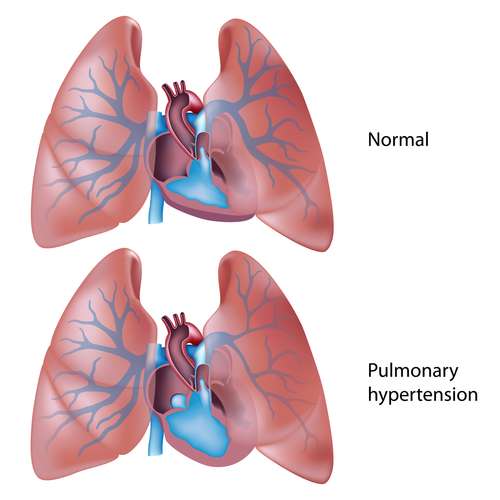

2. Pulmonary hypertension

A person with pulmonary hypertension has abnormally high blood pressure in the arteries of the lungs. The condition makes the right side of the person's heart work harder than normal to push the blood through, and this will also cause heart failure.

Treatment: This is another lung disease that has a very low survival rate. Doctors often prescribe blood vessel dilator medications to treat the disease. Patients can also be subject to surgeries such as atrial septostomy or a lung transplant.